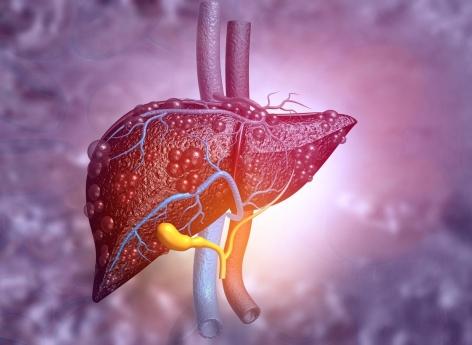

- Rasi Bhadramani/Istock